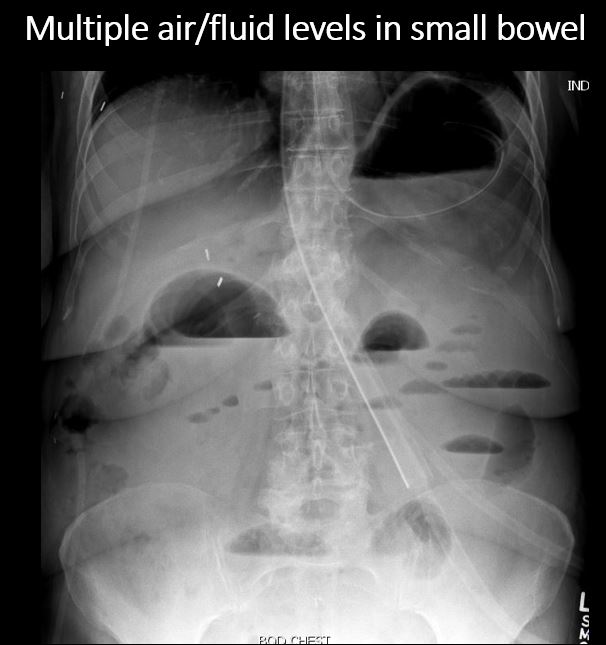

There are more than 3 air/fluid levels or “string of pearls (beads) sign” involving the small bowel. [Yes/No]